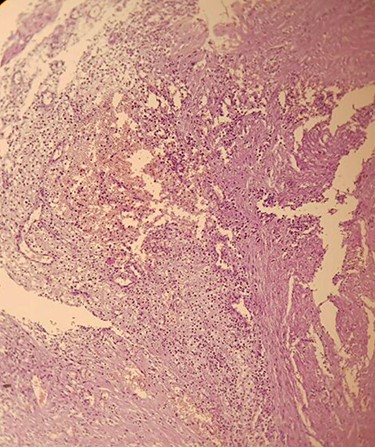

We performed exploratory laparoscopy and found a mass measured (2 × 3 cm) on the left pelvic between the bladder and the uterus, adjacent to the left ovary. A 100-ml serous fluid was found in the pelvis and was aspirated. Furthermore, we noticed formations on the left iliac region adjacent to the parietal peritoneum. We resected the mass and the other formations and sent them to pathology that revealed an aggregation of lipid laden macrophages (foamy cells) (Fig. 2) that is infiltrated by lymphocytes and neutrophils and blood vessels congestion (Fig. 3). These findings suggested Peritoneal Xanthogranuloma with massive necrosis and no ovarian parenchyma. The aspirated fluid was bloody and inflammatory with no signs of malignancy.

Aggregation of lipid laden macrophages (foamy cells) that is infiltrated by lymphocyte and neutrophils with blood vessels congestion.